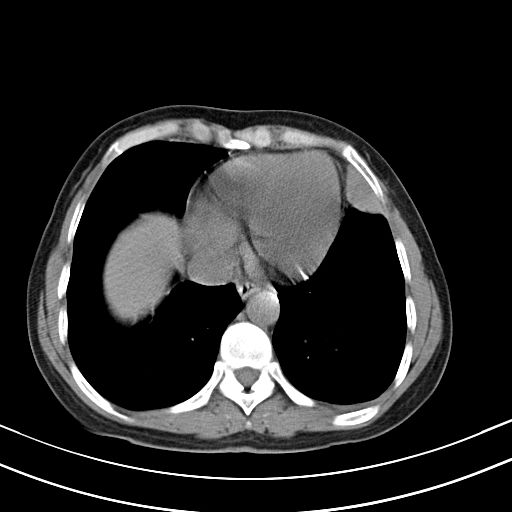

女,47岁,咳嗽胸痛一个星期,我们考虑肺结核,左下肺病灶肿瘤像不像,请高手指点。急。

右肺考虑炎症,建议抗炎后复查,左肺下叶考虑肺不张。

考虑两肺炎症,左胸腔积液,建议治疗后复查!

考虑炎性病变,左肺舌叶病灶需要与早期肺脓肿鉴别(结合实验室),左侧少量胸腔积液。

1)右肺上叶前段及左肺上叶舌段感染性病变;建议抗炎治疗后复查。2)左侧少量胸腔积液。